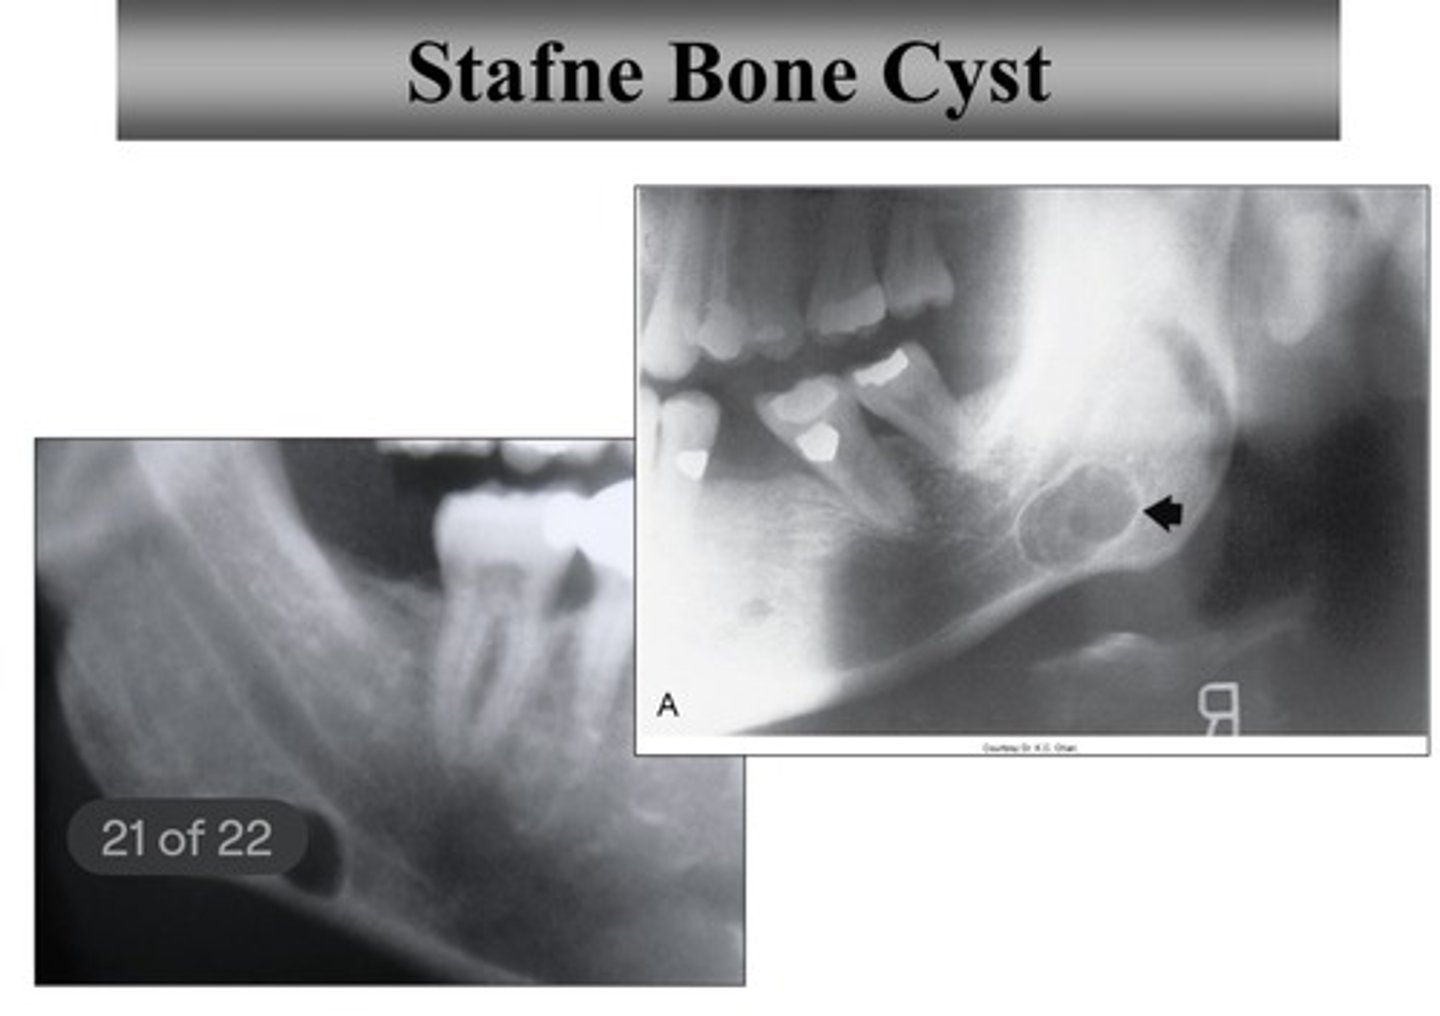

Which cyst is NOT a true cyst?

stafne bone cyst - it is not lined with epithelium and does not contain any liquids

Stafne bone cyst:

- cause: developmental concavity containing normal salivary tissue

- population: men (80-90% of the time)

- location: anterior to angle + inferior to mandibular canal (unilateral or bilateral)

- clinical features: asymptomatic

- radiographic features: well-defined cyst-like radiolucency